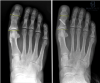

Surgeons can easily fixate oblique osteotomies with a screw. Transverse osteotomies lend themselves to staple fixation although surgeons trained on monofilament wire find that technique satisfactory.6 Percutaneous K-wire fixation is much less common since rigid internal fixation is commonplace. Surgeons have also used sutures. Roy and Tan noted that suture fixation has the advantages of a lower implant signature and a lower cost.7 The authors conceded that the thin cortex of the phalanx can be prone to failure during suture application. Surgeons often do not prefer plate fixation of primary hallux osteotomies as plates are bulkier than screw fixation and can cause soft tissue irritation. Low profile plates may be a more practical plating solution.